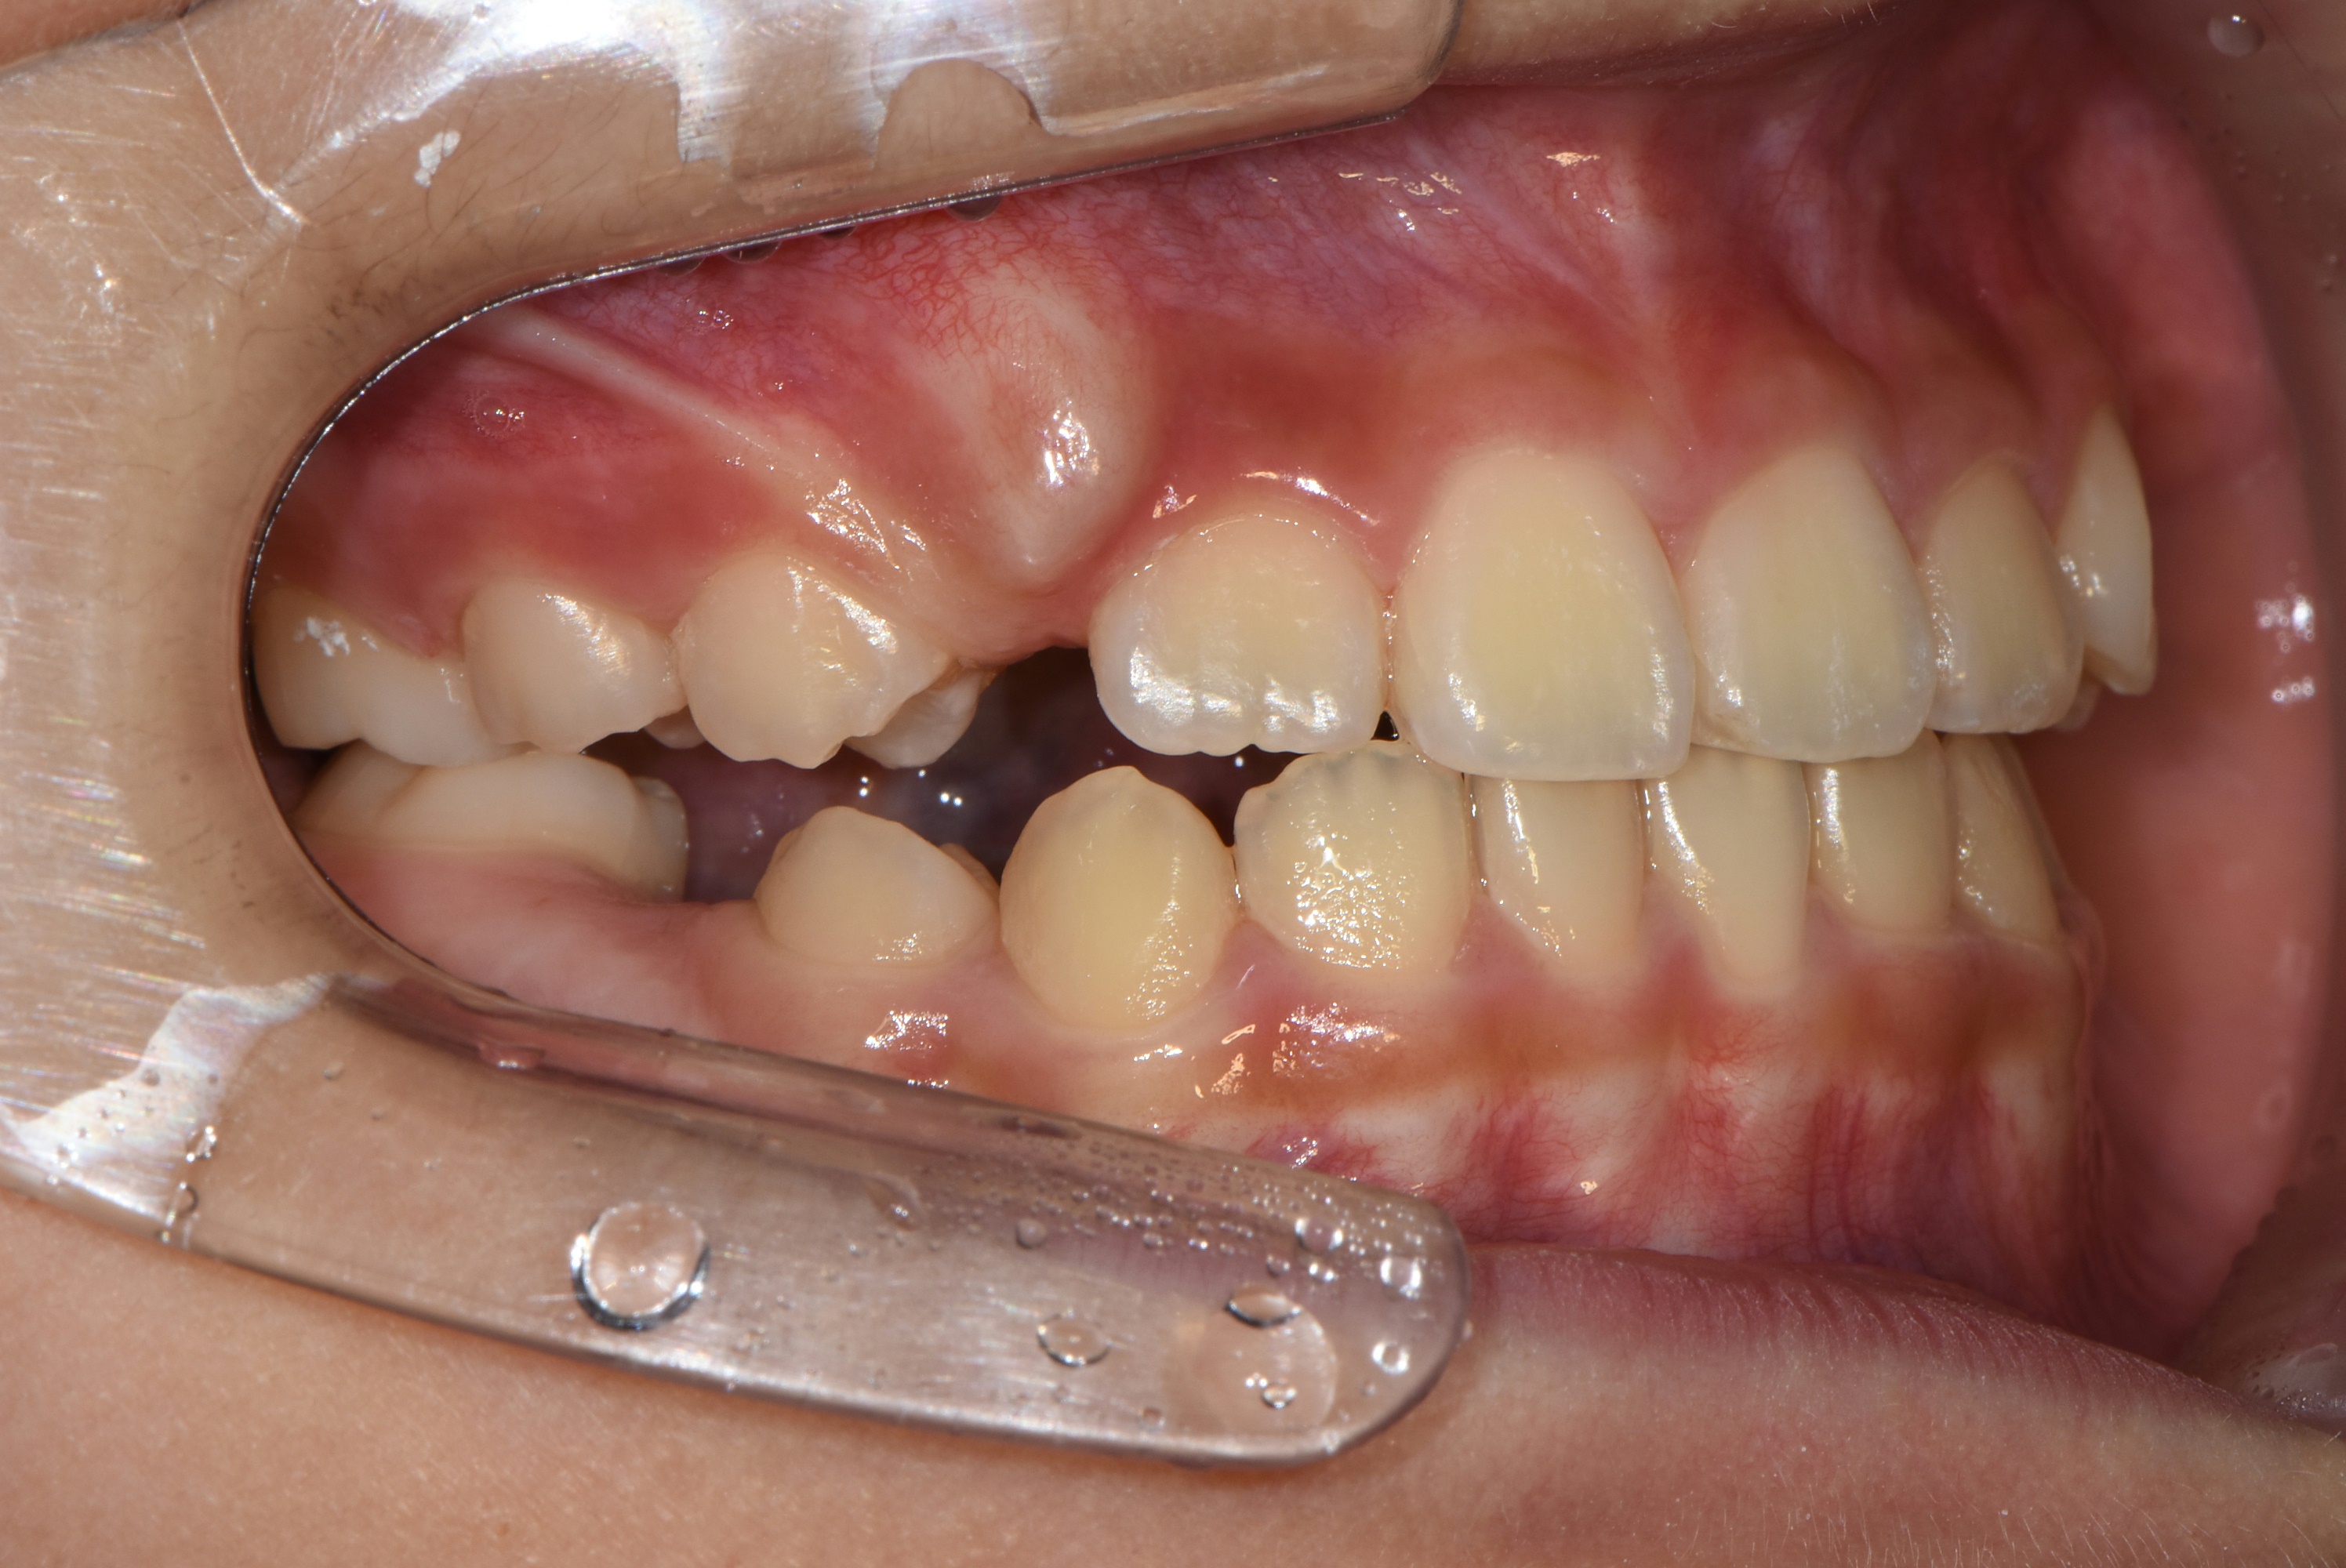

치료 전 사진입니다.